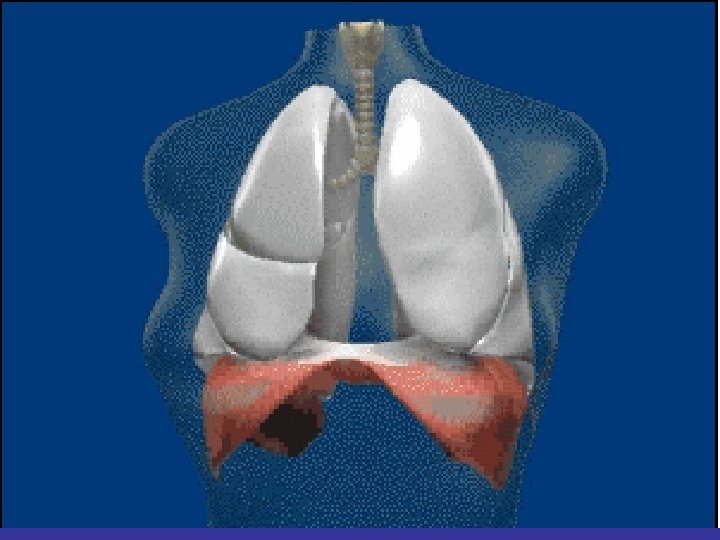

Lobes and Fissures